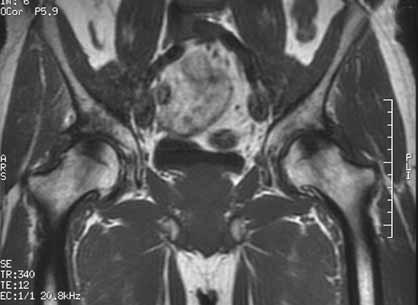

RESONANCIA MAGNETICA  muy sensible a los cambios isquémicos tanto en zonas epifisarias como en zonas metafisodiafisarias.  diagnóstico precoz: 2-5 días.  El patrón de imagen puede variar según el grado de afectación y la respuesta individual.  Una doble linea entre el hueso isquemico y no isquemico.  correlación entre las imágenes de RMN y los hallazgos histopatológicos  Visualiza la integridad del cartílago articular y permite identificar cuerpos libres intraarticulares.

RESONANCIA MAGNETICA